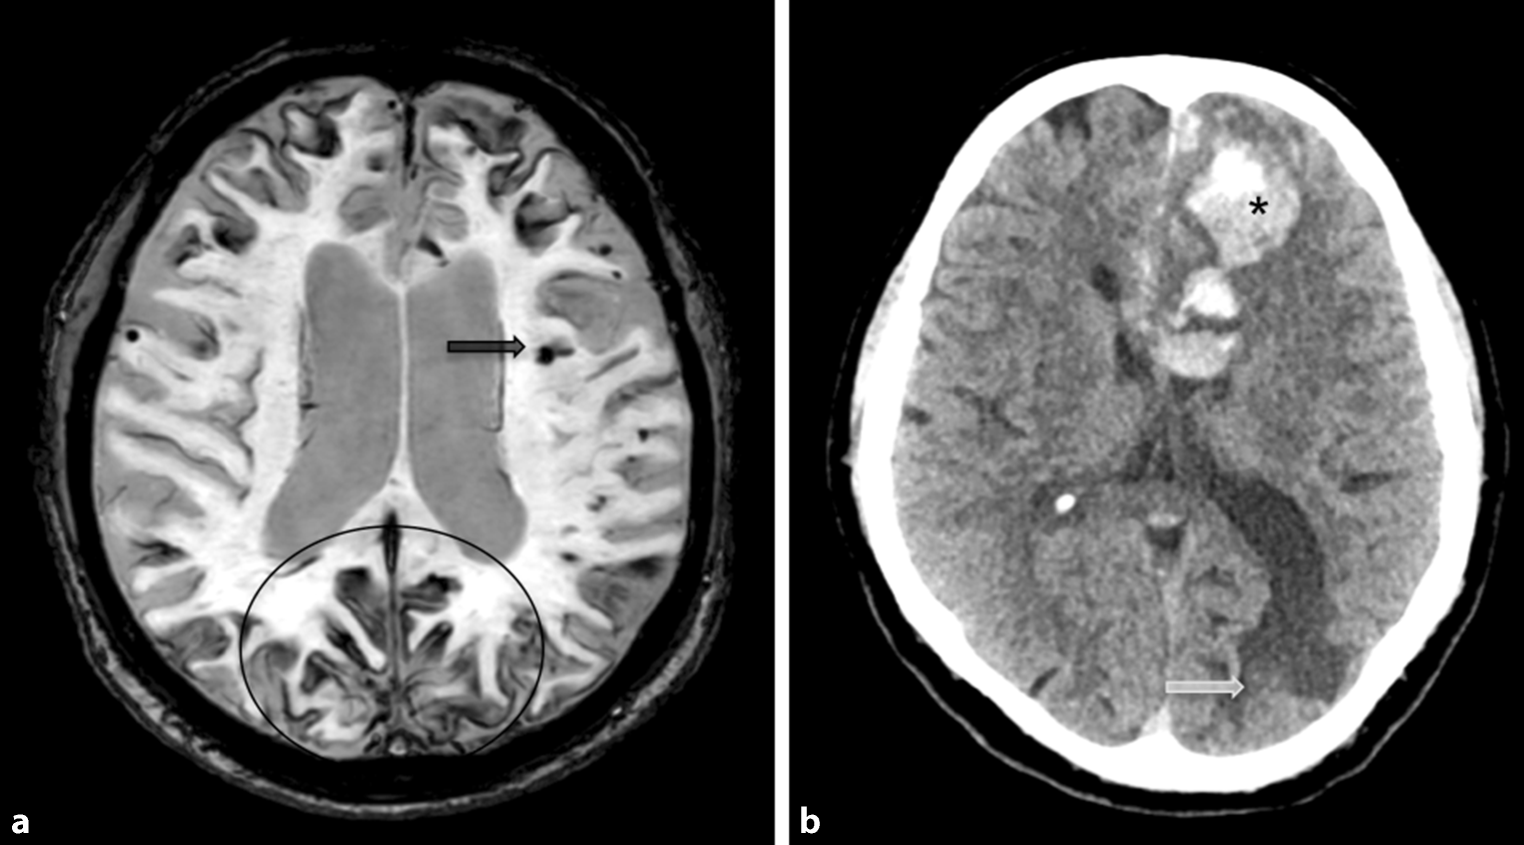

Fig. 11

Cerebral amyloid angiopathy. A 60-year-old female patient with cerebral amyloid angiopathy who presented with superficial hemosiderosis, particularly frontal and occipital (the latter marked with a circle), as well as multiple microbleeds (black arrow) representing hemosiderin deposits on axial susceptibility-weighted images (a). There was also an acute intracranial bleeding in the left frontal lobe (Asterisk), as well as a post-hemorrhagic parenchymal defect in the left occipital lobe (white arrow) on axial computed tomography images (b)

Neuroimaging is notable for diffuse, progressive white matter hyperintensities, microbleeds located in the cortical gray-white matter junction, superficial hemosiderosis, as well as acute intraparenchymal bleeding or post-hemorrhagic parenchymal defects (illustrated in Fig. 11) [14, 15].